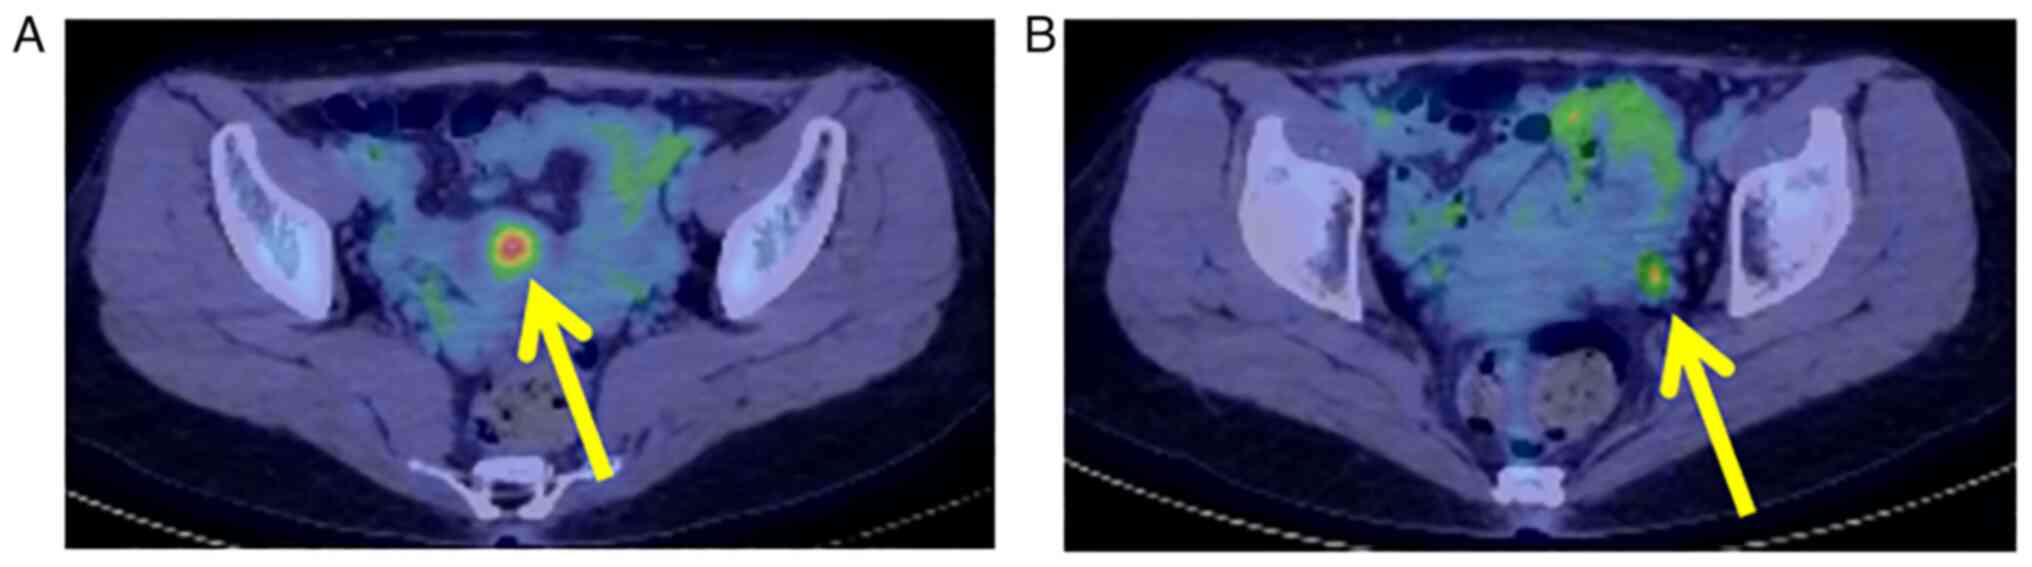

The association between endometrial cancer and the BRCA1 and BRCA2 genes is not fully understood, and the risk elevation of endometrial cancer in patients with hereditary breast and ovarian cancer (HBOC) is not understood. The present report examines a rare case of HBOC syndrome and an uncharacterized variant of the BRCA1 gene in a patient diagnosed with endometrial cancer. A 46‑year‑old woman, gravida 1 para 1, was referred to Wakayama Medical University Hospital (Wakayama, Japan) because positron emission tomography/computed tomography (PET/CT) showed a high FDG uptake in the corpus uteri and the left ovary. PET/CT was performed just after mastectomy for left‑sided breast cancer (triple negative). The patient had previously undergone partial mastectomy for right‑sided breast cancer (triple negative) and was treated with radiation therapy to the right residual breast when she was 39 years old. Laparoscopic hysterectomy and bilateral adnexectomy were performed, and the histological diagnosis was endometrioid carcinoma, grade 1. Her germline BRCA status was tested by blood examination and the result was ‘NM_007294.4(BRCA1):c.49G>C (p.Ala17Pro)’. The variant was evaluated as ‘likely pathogenic’. The patient was diagnosed with HBOC syndrome and endometrial cancer, pT1ANxM0. The patient had no recurrence of breast or endometrial cancer 16 months after gynecologic surgery.